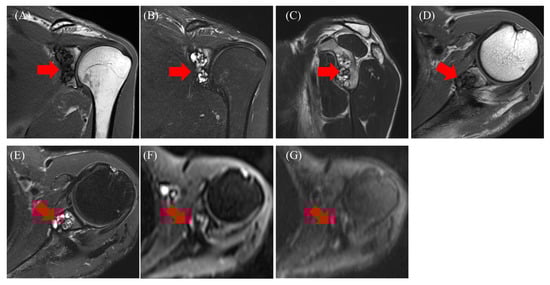

2.1. Case 1

2.2. Case 2